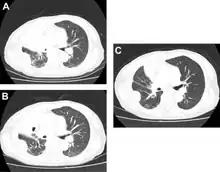

-

Docetaxel for non-small-cell lung cancer a) before b) tumor response after two cycles c) after 4 cycles -